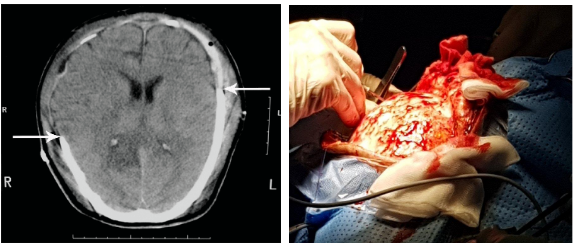

Với các Chấn thương sọ Não có tụ máu dưới màng cứng, ngoài màng cứng hoặc tụ máu lớn trong Não gây hiệu ứng choán chỗ và đè đẩy nhiều thì chỉ định phẫu thuật mở sọ là bắt buộc để tránh tình trạng tăng áp lực nội sọ. Sau đó tùy tình trạng bệnh nhân mà xương sọ có được ghép trở lại vào ngay lập tức hay đợi đến khi tình trạng bệnh ổn định mới phẫu thuật.

Phẫu thuật Chấn thương sọ não vá khuyết sọ nhằm mục đích sửa chữa một khuyết hổng xương sọ sau Chấn thương sọ não hoặc phẫu thuật mở sọ giải áp. Hiện nay có hai phương pháp chính để tạo hình khuyết hổng xương sọ là ghép sọ tự thân hoặc ghép sọ bằng các vật liệu nhân tạo như xi măng sinh học, vật liệu carbon, vật liệu PEEK hoặc lưới Titanium,...

Phẫu thuật ghép sọ tự thân thường được áp dụng sau các phẫu thuật mở sọ giải áp điều trị phù não do chấn thương. Mảnh sọ sau khi được cắt ra sau phẫu thuật lần đầu sẽ được chuyển tới các ngân hàng mô để bảo quản, cụ thể là tiệt trùng bằng tia Gamma và giữ cấp đông ở nhiệt độ -85 độ C nhằm bảo quản mảnh xương sọ với thời gian lên tới 5 năm. Tuy nhiên khuyến cáo phẫu thuật đặt lại bản sọ tự thân tốt nhất nên được thực hiện trong khoảng thời gian 3-9 tháng sau lần mở sọ đầu để tránh nguy cơ viêm rò, tiêu sập xương sọ do phản ứng đào thải của cơ thể.

Thông thường mảnh xương sọ được đặt lại vị trí cũ cho bệnh nhân thường vừa đủ với vị trí khuyết sọ nhưng khi có các biến chứng như viêm rò, tiêu sập mảnh ghép xương sọ sau phẫu thuật vá khuyết sọ thì cần phải tháo bỏ mảnh ghép để điều trị viêm ổn định rồi mới tiến hành vá khuyết sọ bằng vật liệu nhân tạo sau 9-12 tháng